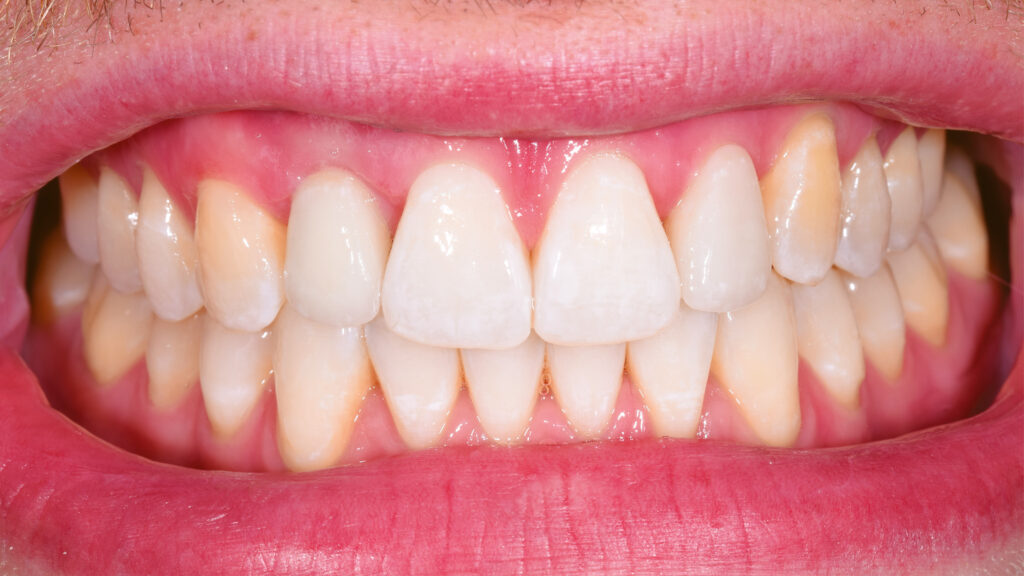

Paradigmenwechsel:

Nach der Heilung des Weichgewebes sind die arkadenförmige Kontur der Gingiva und die Papillen deutlich zu erkennen (Abb. 42 und 43). Etwa sechs Monate nach der Osseointegration und Konditionierung der Gingiva wird die Situation mit dem Intraoralscanner erfasst, um mit der Herstellung der implantatprothetischen Versorgung fortzufahren. Nach dem Aufschrauben des Scanbodys auf das Implantat erfolgt der Scanvorgang (Abb. 44). Intraoralscanner gehören zu den aufregendsten neuen Technologien in der Zahnmedizin. Die digitale Abformung bietet dem Patienten deutlich mehr Komfort. Zudem werden klinische Abläufe vereinfacht und die Kommunikation mit dem Zahntechniker verbessert. Im nächsten Schritt werden die STL-Dateien für den Modelldruck aufbereitet (Abb. 45). Vor dem Scannen der gedruckten Modelle muss das Modellanalog regio 12 eingesetzt werden. Das Modell mit abnehmbarer Gingivamaske ist für die Aufnahme des Modellanalogs durch eine Öffnung vorbereitet und besitzt im unteren Bereich des Ausschnittes eine Art Verriegelungsmechanismus (Abb. 46). Dies gewährleistet einen sicheren Presspassung und eine korrekte, automatisch zentrierte Einschubposition (Abb. 47).

Eingliederung der Implantatkrone

Nach einigen Monaten war das periimplantäre Weichgewebe endgültig stabilisiert. Es zeigte sich noch eine leichte Narbenbildung am Gingivazenit. Nach vorsichtigem Ausdrehen der provisorischen TempShell-Krone offenbart sich eine gut ausgebildete Weichgewebsarchitektur. Die Gewebedicke an der Implantationsstelle ist vergleichbar mit der Situation am zu kopierenden linken lateralen Schneidezahn (Abb. 64). Die Zirkonoxidkrone mit Titanadapter wird definitiv mit dem Implantat verschraubt. Durch die detaillierte digitale Vorbereitung sind oft nur kleine Korrekturen notwendig. Meist können die Restaurationen ohne Einprobe eingegliedert werden. Die biokompatiblen Anteile der Implantatkrone (Titanadapter) und die subgingivalen Anteile der Implantatkrone gewährleisten eine optimale Anlagerung der Gingiva (Abb. 65). Der spaltfreie Sitz der Versorgung auf dem Implantat wird röntgenologisch kontrolliert.

Abschließend kann der Schraubenkanal mit Teflonband und Komposit verschlossen und die statische und dynamische Okklusion überprüft werden. Bei der Eingliederung einer Frontzahnimplantatkrone kommt es vor allem auf eine ästhetische Integration an. Neben der weißen Ästhetik ist die rote Ästhetik mit der Ausformung des Emergenzprofils und der Harmonie des Gingivaverlaufs wichtig. Die Restauration fügt sich ästhetisch gut in die Zahnreihe ein (Abb. 66 bis 68). Das Zusammenspiel der dentalen und gingivalen Umgebung sowie der Lippen mit der prothetischen Versorgung ergibt ein harmonisches Gesamtbild (Abb. 69). Einige Monate nach dem Einsetzen der Implantatkrone hat sich die Gingiva sichtbar gut erholt (Abb. 70).